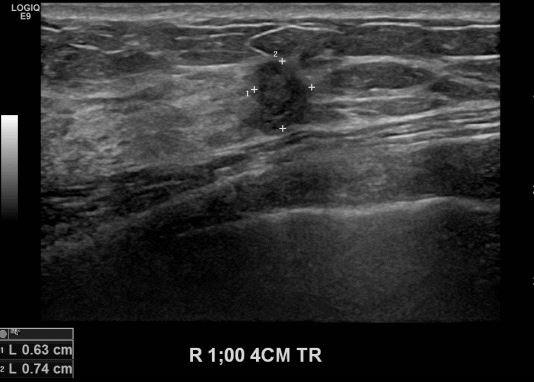

상기환자 건강검진상 이상소견으로 내원하신 40대 여성분으로 본원 초음파상 우측 1시방향에서 4cm 떨어진 거리의 의심스러운 멍울 조직검사 시행하여 우측 침윤성 유관암 진단되었습니다.